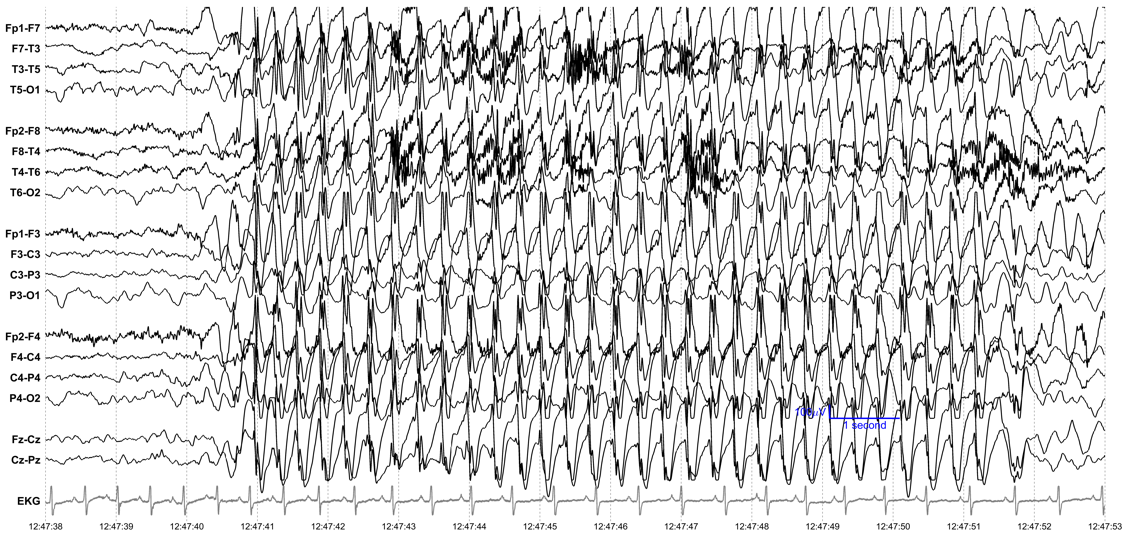

Algorithms can also detect harmful brain activity like a seizure, as shown in Figure 2.

Figure 2. A 15-second excerpt from an EEG recording from a 22-year-old man. The high-amplitude rhythmic brain activity is a seizure. Detecting this kind of abnormal electrical activity in the brain helps establish a diagnosis of epilepsy and helps doctors choose a treatment that can prevent future seizures.